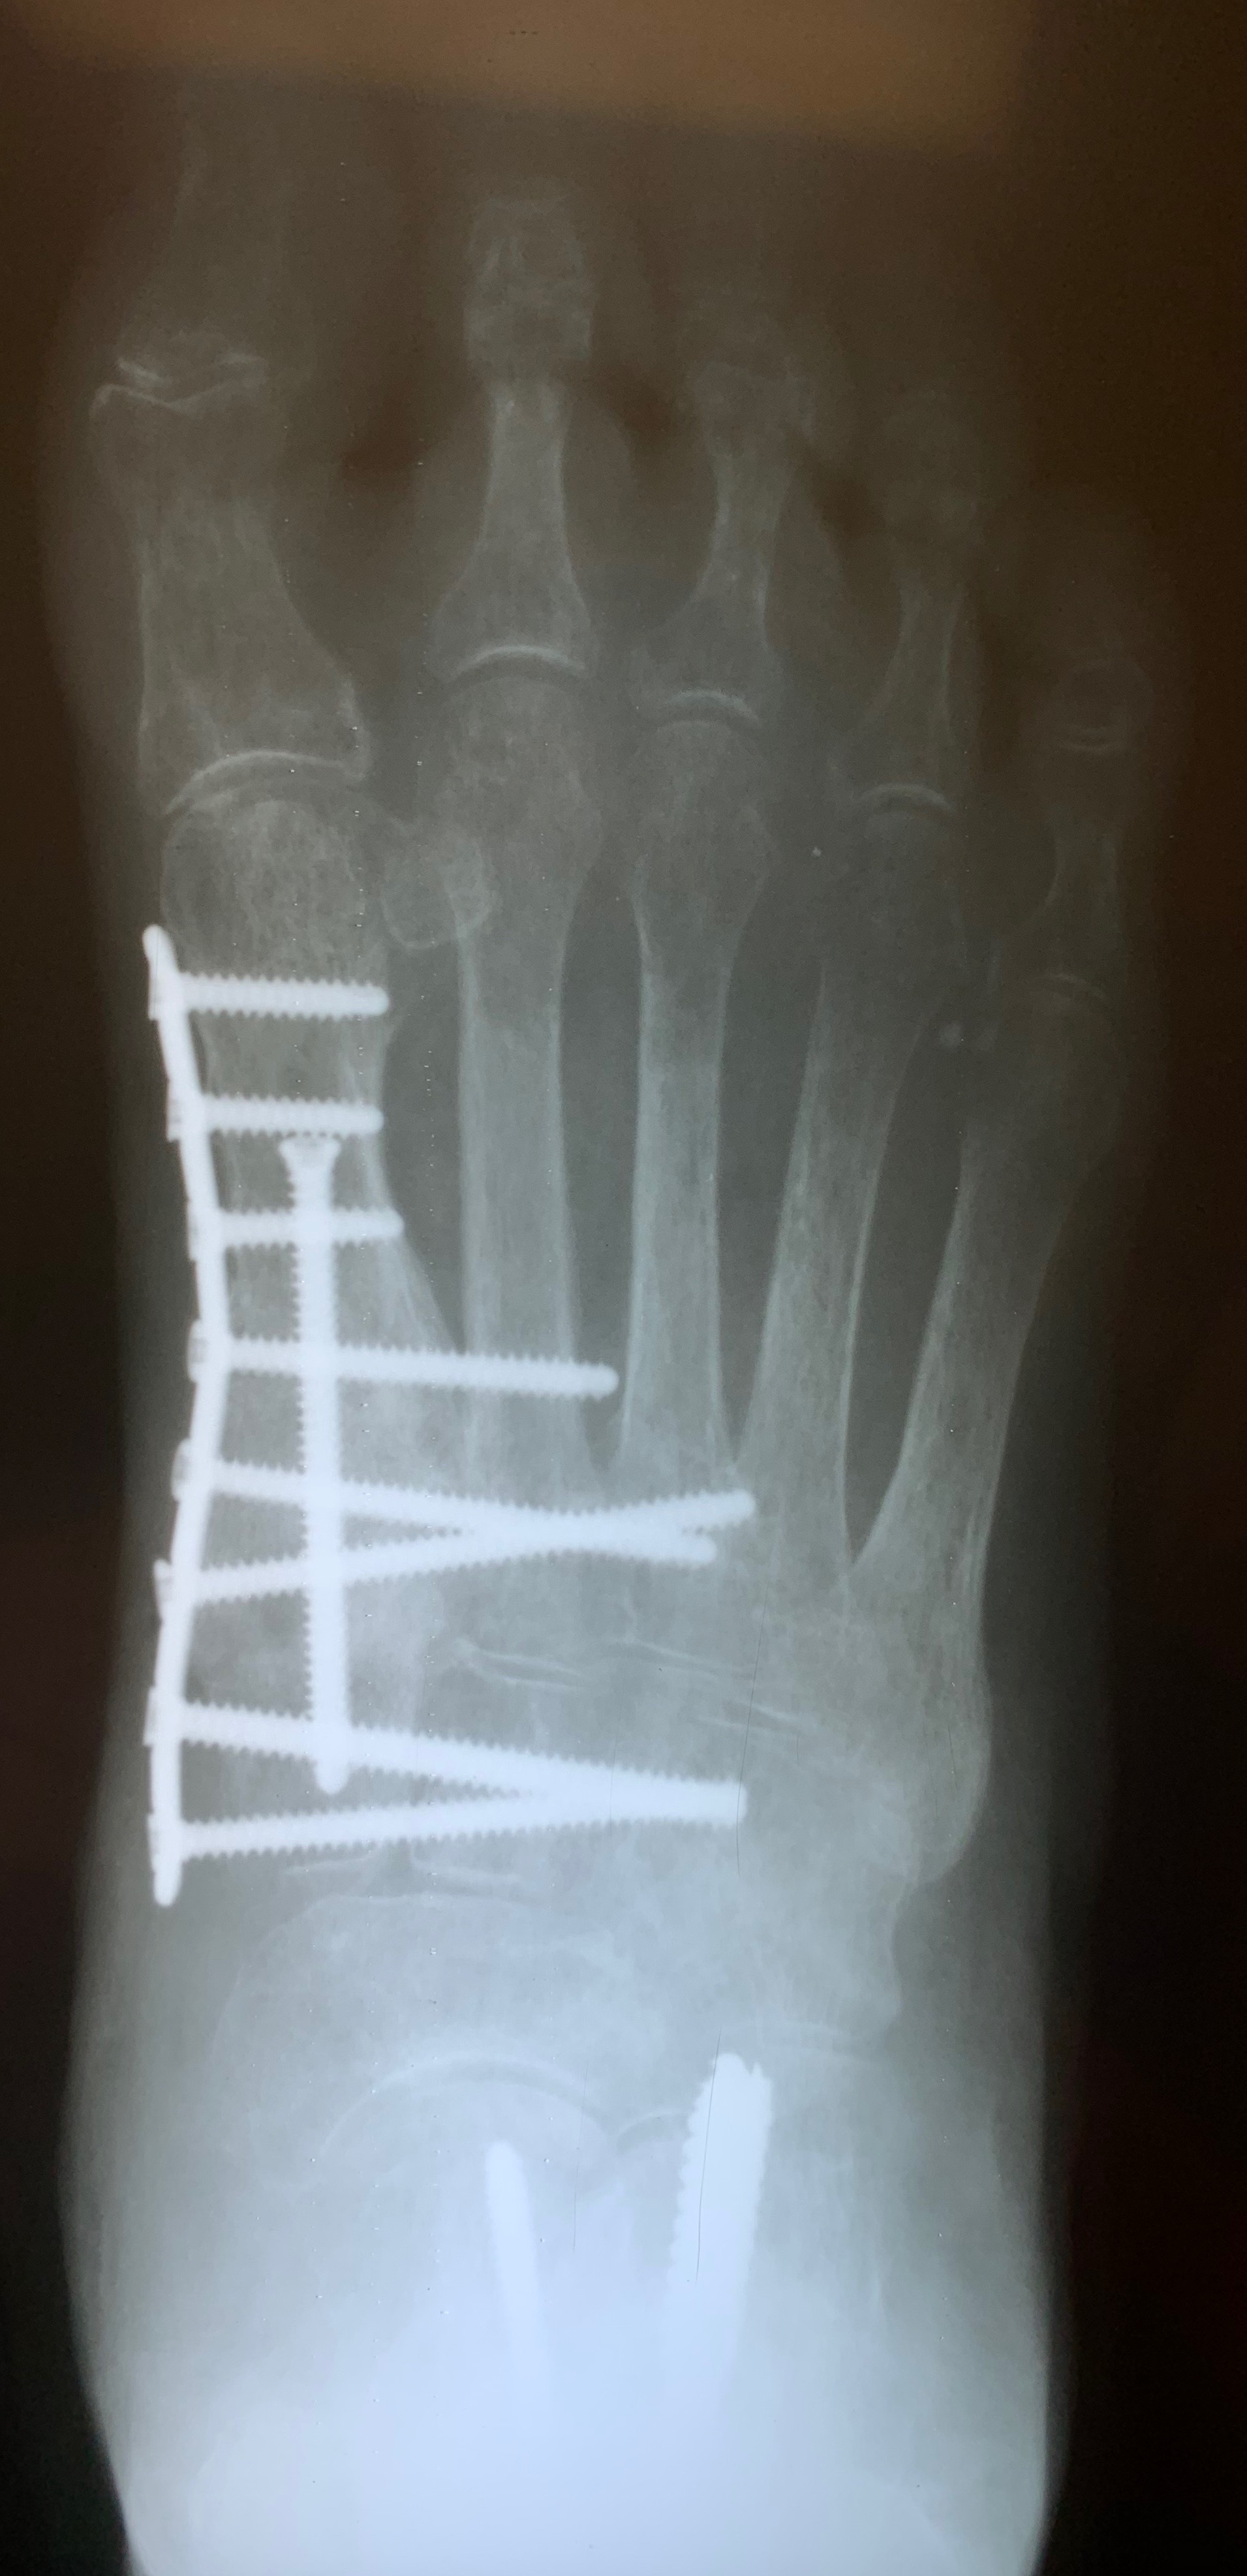

(59yearold female, chronic plantar foot pain, flat and splay foot Foot Bone Graft Healing Time What happens after a bone grafting procedure? Foot fusion surgery is when separate bones in the foot are permanently joined together (fused). It can be used to treat arthritis (including. Over time, the graft material grows into (fuses with) nearby bone tissue. To do this, you should use the surgical sandal you are provided with. Inflammation, bone production and bone. Foot Bone Graft Healing Time.